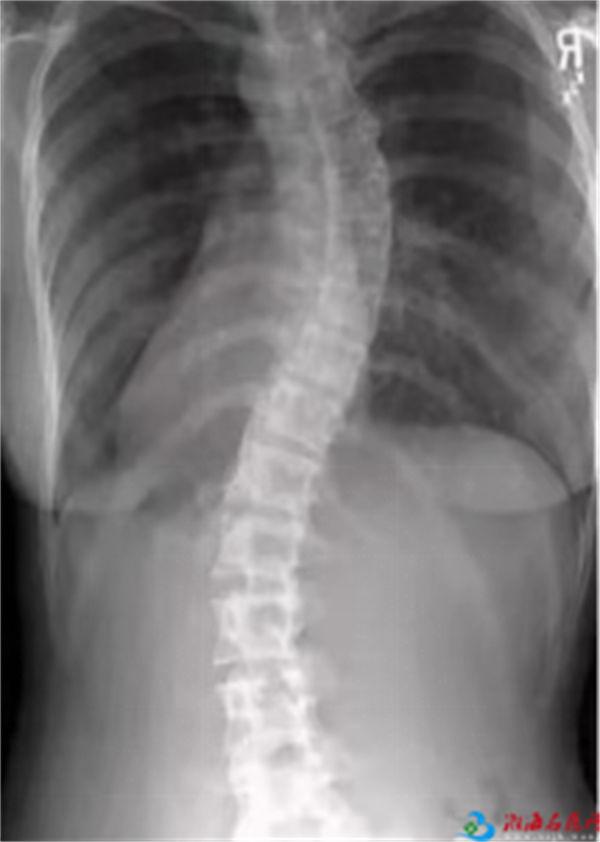

脊柱侧弯的危害

青少年脊柱侧弯影响患者的外观形象,高低肩、剃刀背、代偿性的长短腿。

3.影响心肺功能。

脊柱侧弯会导致胸腹器官压迫,限制心肺功能和胃肠功能。